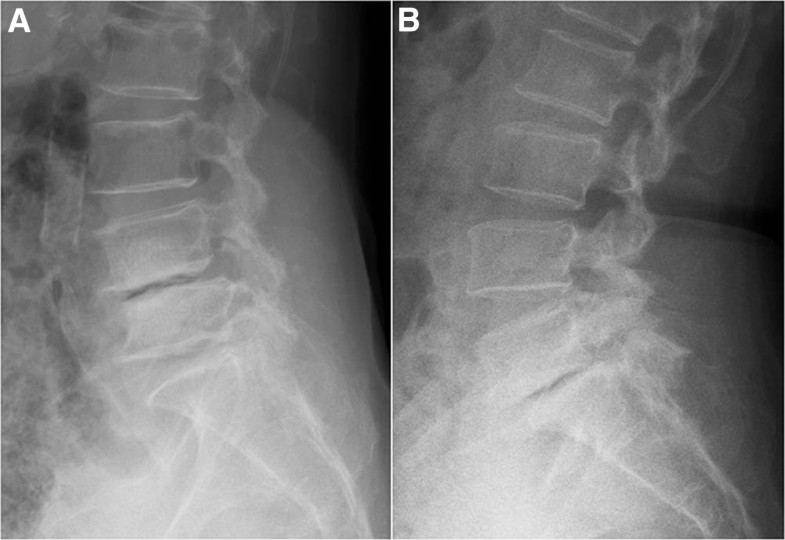

Is Vacuum Disc Phenomenon Dangerous .  vacuum disc phenomenon is seen frequently with degenerative disc disease and is characterized by the collection of gas in.   ‘vacuum phenomenon’ or ‘pneumoarthrosis’ term is used when there is air within a joint space.  vacuum disc phenomenon at multiple lumbar spinal levels with nitrogen bubbles (arrows) leaking into the spinal fluid.   vacuum phenomenon on radiographic studies is associated with a vertical instability and collapse, resulting.   intervertebral vacuum phenomenon is defined as a collection of gas within the intervertebral disc and was first.

‘vacuum phenomenon’ or ‘pneumoarthrosis’ term is used when there is air within a joint space.  vacuum disc phenomenon is seen frequently with degenerative disc disease and is characterized by the collection of gas in.  vacuum disc phenomenon at multiple lumbar spinal levels with nitrogen bubbles (arrows) leaking into the spinal fluid.   intervertebral vacuum phenomenon is defined as a collection of gas within the intervertebral disc and was first.   vacuum phenomenon on radiographic studies is associated with a vertical instability and collapse, resulting.

Is Vacuum Disc Phenomenon Dangerous   vacuum disc phenomenon at multiple lumbar spinal levels with nitrogen bubbles (arrows) leaking into the spinal fluid.   ‘vacuum phenomenon’ or ‘pneumoarthrosis’ term is used when there is air within a joint space.   vacuum phenomenon on radiographic studies is associated with a vertical instability and collapse, resulting.   intervertebral vacuum phenomenon is defined as a collection of gas within the intervertebral disc and was first.  vacuum disc phenomenon is seen frequently with degenerative disc disease and is characterized by the collection of gas in.  vacuum disc phenomenon at multiple lumbar spinal levels with nitrogen bubbles (arrows) leaking into the spinal fluid.